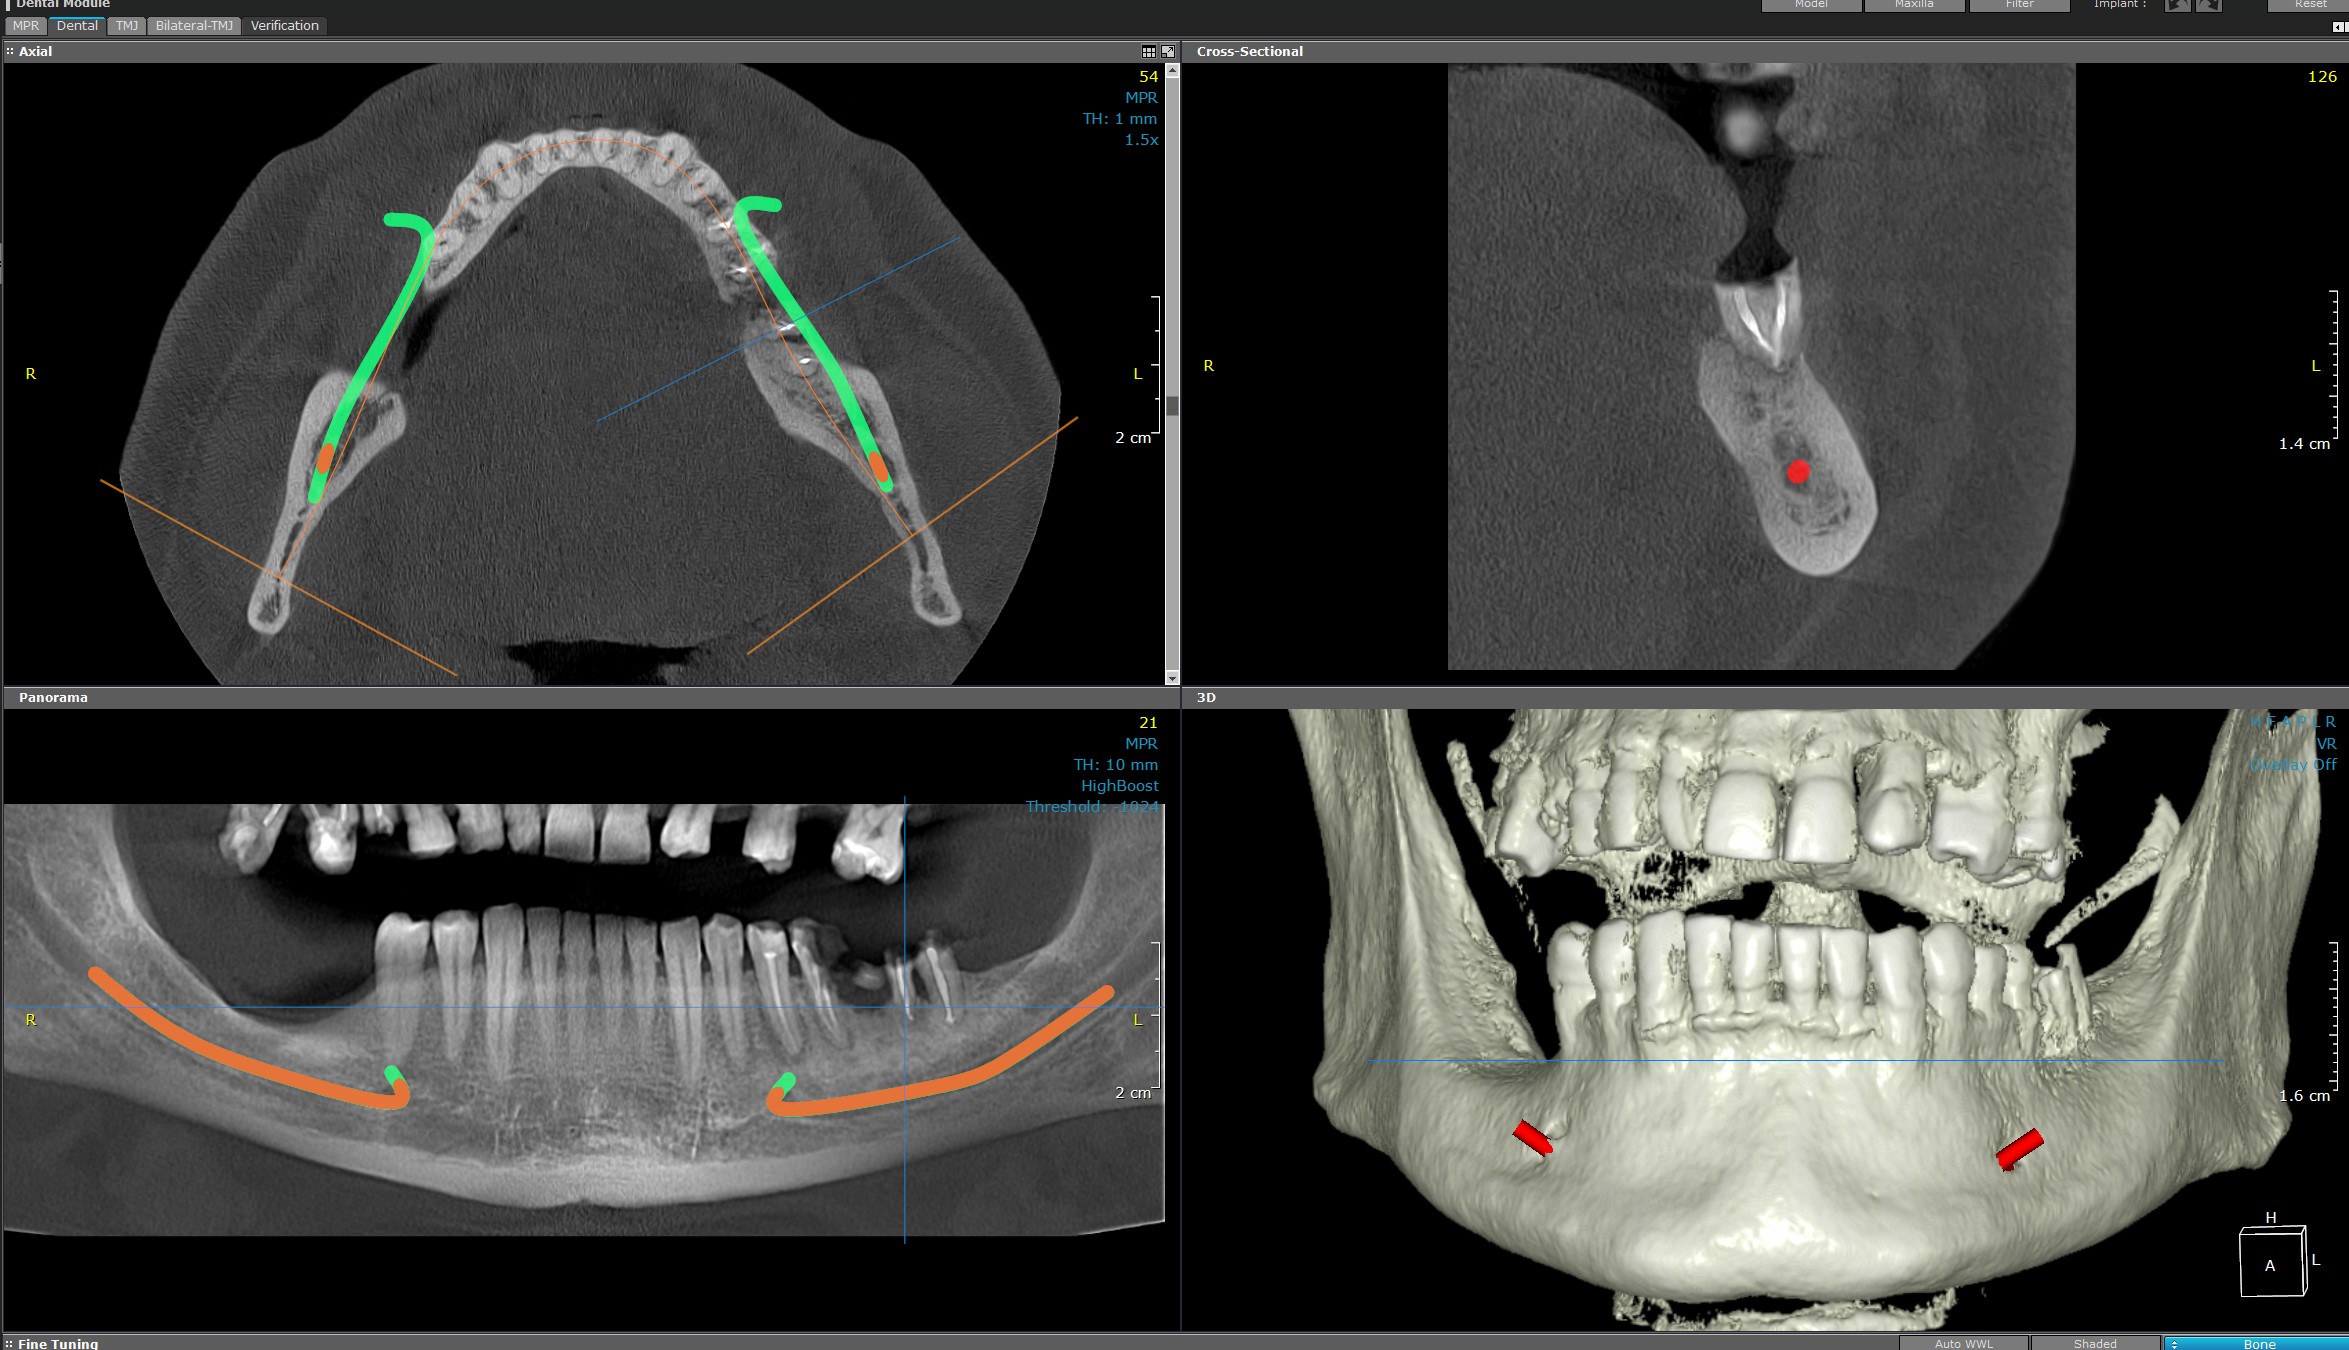

Pe baza imaginilor obținute prin CBCT (Computer Tomograf cu fascicul conic), realizăm o serie de analize 3D personalizate care ajută în diagnosticare și planificarea tratamentelor:

- Analiza densității osoase

Evaluează calitatea osului în zonele de interes, esențială pentru implanturi sau tratamente chirurgicale. - Analize endodontice

Permite examinarea detaliată a canalelor radiculare, vârfurilor radiculare și leziunilor dentare pentru tratamente de canal de mare precizie. - Analiza ofertei osoase pentru implanturi

Se determină volumul și structura osului disponibil pentru a simula cu acuratețe plasarea implanturilor dentare. - Măsurători pe zone de interes

Se efectuează măsurători exacte ale spațiilor anatomice, utile în planificări chirurgicale sau ortodontice.

Analiza volumelor

Identifică și măsoară volumele structurilor anatomice sau ale leziunilor, oferind o imagine completă asupra zonei investigate.